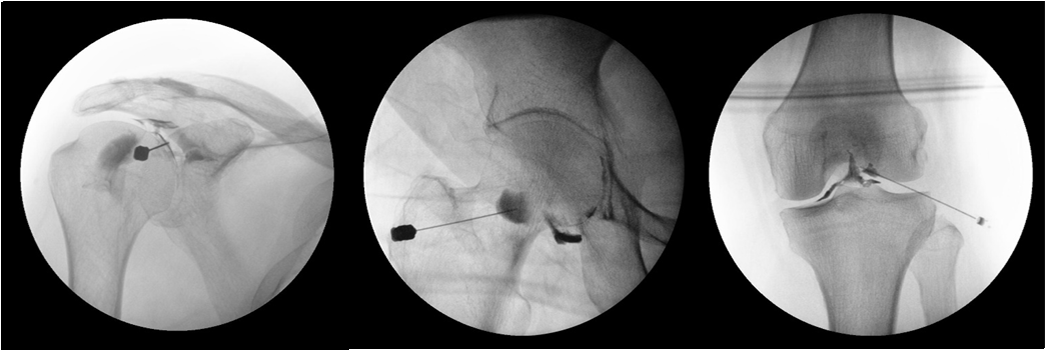

C-arm 유도 주사치료

• 척추와 관절 주위 구조물을 C-arm으로 확인하며 정확하고 안전하게 치료 부위에 약물을 주입할 수 있습니다.